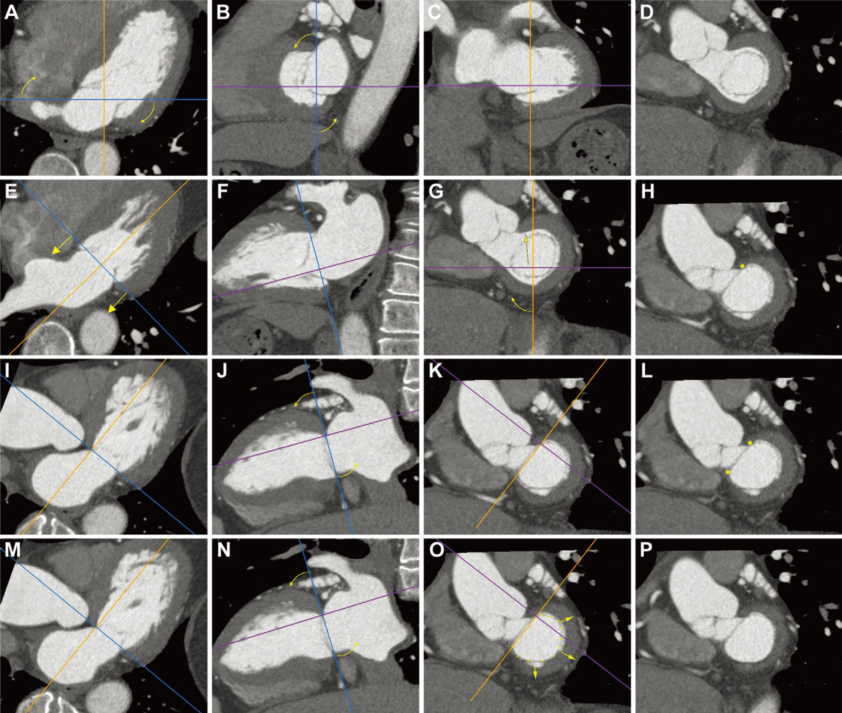

既往对于二尖瓣环解剖的评估主要依赖于超声心动图。但超声对于二尖瓣环形态的评估主要为常规超声心动图的二维径线评估,高质量的三维评估则需进行半侵入性的经食管超声心动图。对于TAVR患者,常规需行MSCT进行主动脉瓣术前相关评估,因此可获取心脏全周期图像。而近年来,MSCT也逐渐应用于二尖瓣环形态评估。不同于复杂的鞍形二尖瓣环模型,基于MSCT的二尖瓣D型瓣环模型可快速简便地评估二尖瓣环形态(图1)。因此,此项研究的目的便是探索MSCT评估的二尖瓣D型瓣环形态与TAVR术后MR改善的关系。

图1 MSCT构建D形二尖瓣环模型主要步骤(A-P):弯曲箭头表示旋转图像,直箭头表示在不改变其角度的情况下移动平面